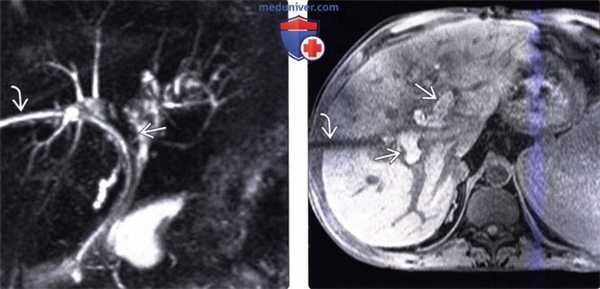

(Слева) На аксиальной КТ с контрастным усилением у женщины, которой четыре года назад была выполнена трансплантация печени, определяется обширный билиарный некроз. Левый печеночный проток неравномерно расширен, в то время как правый«замаскирован» расположенной поблизости биломой. Пациентке была выполнена ретрансплантация.

(Справа) На МРХПГ у пациента, которому ранее была выполнена трансплантация печени, определяется доминирующая ишемическая стриктура и умеренно выраженное расширение внутрипеченочных протоков. При допплерографии не было обнаружено признаков непроходимости печеночной артерии. При исследовании биоптата печени были выявлены изменения, соответствующие ишемическим повреждениям при реперфузии.